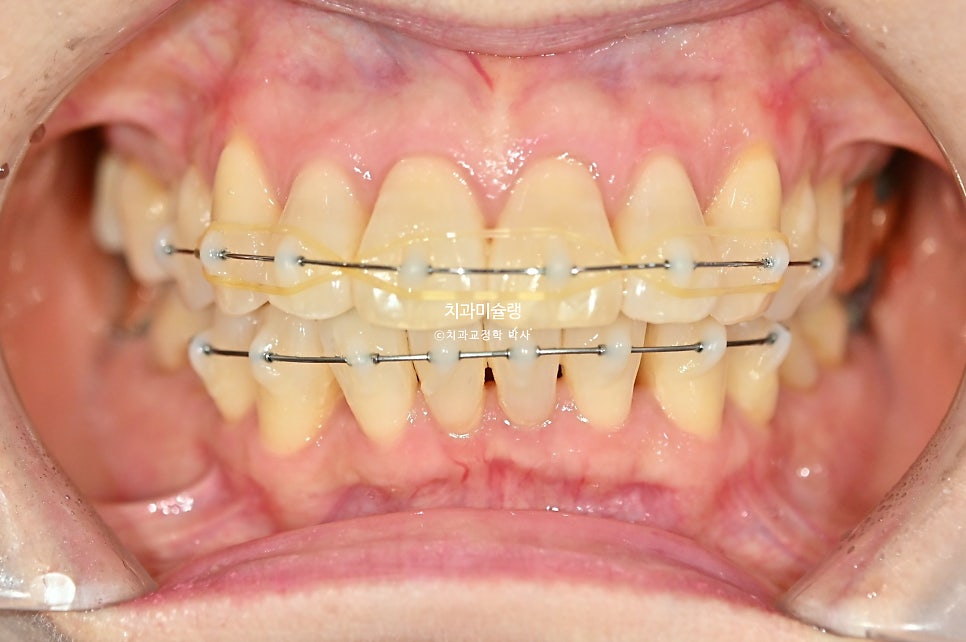

MTA앞니 부분교정 치료 시작하셨습니다.

앞니 부분교정에서 치간삭제는 필수입니다. 과하지 않은 범위 내에서 시행하면 치료에 도움이 되죠.

치료시작 3개월차

장치는 작은어금니에서 작은어금니까지, 앞니 위주로 위아래 8개씩 붙였습니다.

대부분의 교합을 담당하는 큰어금니 및 두번째 작은어금니 들은 장치를 붙이지 않았으므로, 잇몸 부담도 적고 교합 불편감도 없습니다.

중년 교정에서 더더욱 전체교정보다 앞니 부분교정을 추천하는 이유입니다.